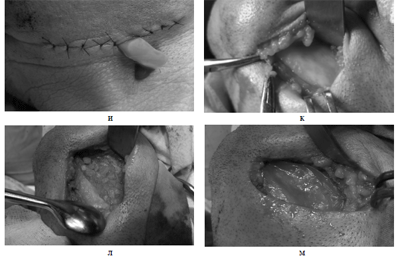

Операция проведена 2.04.09г. под общим эндо- трахеальным обезболиванием наружным доступом. Произведен дугообразный разрез в области угла и тела нижней челюсти справа на 2.5 см ниже нижнего края длиной 6-6.5 см. (рис.За). Мягкие ткани рас-сечены послойно до кости. После отсепаровки надкостницы виднелась бугристая, слегка вздутая наружная кортикальная пластинка ветви нижней че-люсти (рис.Зб). Под охлаждением физиологического раствора высверлили и удалили наружуню корти-кальную пластинку (рис.Зв). Макроскопически по-лость кисты была заполнена серовато-грязной кератиновой массой (рис.Зг). После тщательного вылущивания кисты была проведена резекция нижней челюсти отступая на 0.5-1 см от границ опухоли, сохраняя непрерывность нижней челюсти в области его заднего края (рис. Зд). Образовавшийся дефект был заполнен размельченным аллогенным ДКМ в комбинации с БоТП и поверх закрыт и изолирован от окружающих мягких тканей мембраной из пчелиного воска в целях направленной регенерации кости (рис. Зе,ж,з). Со стороны полости рта был удален

Рис.3. Этапы операции: а)маркирована линия разреза, б) обнажена наружная поверхность кости, в) высверливание кортикальной пластинки г) видна оболочка кератокисты, д) проведена резекция нижней челюсти, е) заполнение дефекта размельченным ДКМ с БоТП, ж,з)наложение мембраны из пчелиного воска поверх костно-пластического материала, и)ранаушита послойно с оставлением резинового выпускника, к) обнажено тело нижней челюсти слева, л) кистозная полость заполнена ДКМ с БоТП, м) наложена восковая мембрана.

46 периодонтитный зуб. Рану послойно ушили с оставлением резинового выпускника (рис.Зи). Аналогичным образом проведена операция с левой стороны внеротовым доступом с одной лишь разницей, что при удалении наружней кортикальной пластинки была выявлена оболочка радикулярной кисты с ки-стозным содержимым. Была проведена цистэкто- мия с апекэктомией 35 зуба. Остаточную костную полость заполнили аллогенным ДКМ с БоТП и изо-лировали от надкостницы мембраной из пчелиного воска (рис.3 к,л,м).